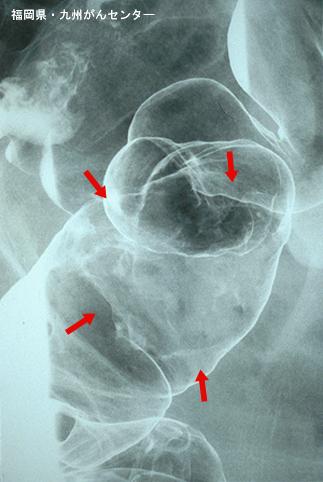

Posted by: Fukuoka Pref., Centro Kyushu de Curaciones de Cáncer

clasificación del pacienteTumor Epitelial Maligno/Adenocarcinoma

parte(separada por órganos)colon/sigmoides

método de exámenRayos X

clasificación ectoscópica de tumoresTipo 1(Tipo protuído)/

diámetro mayor del tumor40 -

grado de penetraciónss(a1)